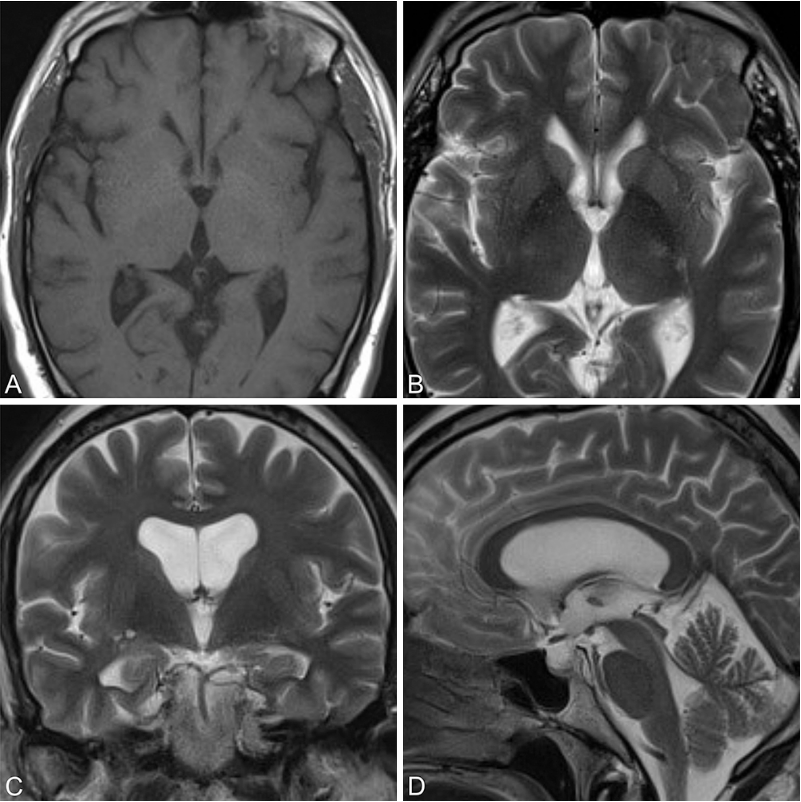

术后3年获取的 T1 加权(A 为轴位)和 T2 加权(B 为轴位;C 为冠状位;D 为矢状位)磁共振图像显示无囊肿复发。